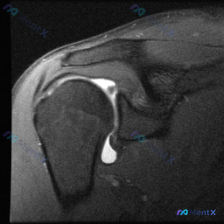

整理了一份肩关节MRI病例讨论材料,先放轴位T2加权像的分析。 核心发现: - 扫描层面在盂肱关节中部,显示肱骨头、关节盂、前后盂唇 - 前盂唇(图像左侧)可见明显不连续高信号,穿透盂唇结构 - 后盂唇形态完整,信号均匀;肩胛下肌、肱二头肌长头腱未见明显异常 讨论焦点:这个前盂唇病变更像真性撕裂(如...

最近整理了一份右肩部MRI的病例资料,是冠状位T1加权图像。用户最初关注的是盂唇病变(Labral pathology),但影像分析有几个有意思的发现: 1. 冈上肌肌腱远端(接近肱骨大结节止点)信号异常增高,形态大致连续 2. 肱骨头骨髓内可见多个圆形/椭圆形低信号影(软骨下囊肿),周围有轻微骨硬...